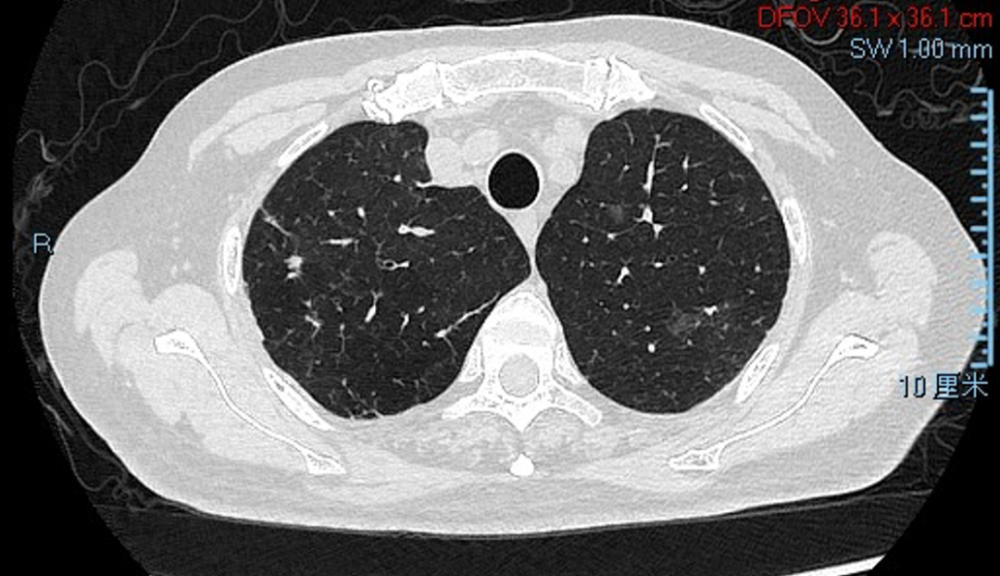

胸部CT(2021-1-13)

胸部CT(2021-1-25)

胸部CT(2021-2-23)